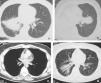

Caso 1: tomografía computarizada de tórax (a) con contraste que muestra una masa espiculada de gran tamaño alrededor del bronquio intermediario; 9 meses después (b) se detecta una masa espiculada contralateral que entra en contacto con el bronquio de la língula. El paciente fue tratado con prednisona. Caso 2: la tomografía computarizada torácica (c) muestra una lesión endobronquial con calcificaciones puntiformes en el bronquio lobular inferior (flecha), que produce una atelectasia parcial postobstructiva del lóbulo inferior derecho (d).

En la figura 1a se muestra el estudio inicial de tomografía computarizada (TAC) torácica de un varón de 51 años con neumonías recurrentes. Se observa una masa hiliar derecha espiculada que produce una discreta compresión extrínseca sobre los bronquios del lóbulo medio y del lóbulo inferior izquierdo. Había adenopatías paratraqueales derechas bajas (no mostradas). La punción aspirativa con aguja fina transtorácica guiada por TAC demostró únicamente la presencia de células inflamatorias. Se llevó a cabo una neumonectomía, con el posterior diagnóstico patológico de TMI. Nueve meses después se detectó una recurrencia pulmonar contralateral, que se controló con corticoides (fig. 1b). En una larga serie de TMI torácicos, Agrons et al1 describen que sólo el 20% de éstos presentan bordes espiculados. El compromiso bronquial secundario a una lesión del parénquima pulmonar ocurre en el 10% de los casos, y la presencia de adenopatías en sólo el 7%. En otra serie4 de 23 pacientes no se describe ningún caso con adenopatías mediastínicas. El diagnóstico diferencial de una masa espiculada es amplio. En el adulto, se debe descartar en primer lugar una neoplasia primaria o una metástasis. En un niño, una lesión de estas características representa de forma más probable un TMI, en especial si no hay otros signos de malignidad1. Desde el punto de vista radiológico, una lesión espiculada con aporte arterial puede ser indistinguible de un secuestro pulmonar intralobular1.

En la figura 1c se muestran unos cortes axiales de TAC de un varón de 30 años con historia de tos y expectoración de 5 meses. En el bronquio del lóbulo inferior derecho se observa una lesión endobronquial parcialmente calcificada que produce una atelectasia lobular parcial con bronquiectasias. La biopsia demostró una reacción inflamatoria inespecífica. Tras realizar una lobectomía del lóbulo inferior derecho se obtuvo el diagnóstico de TMI (fig. 1d). Los TMI torácicos endobronquiales son extremadamente infrecuentes1, no así la presencia de calcio intralesional, que puede ocurrir hasta en un 15% de las lesiones del parénquima. El TMI endobronquial puede simular un tumor carcinoide, carcinoma adenoide quístico o carcinoma mucoepidermoide. La presencia de calcificaciones en una lesión pulmonar orienta a granuloma o hamartoma1.